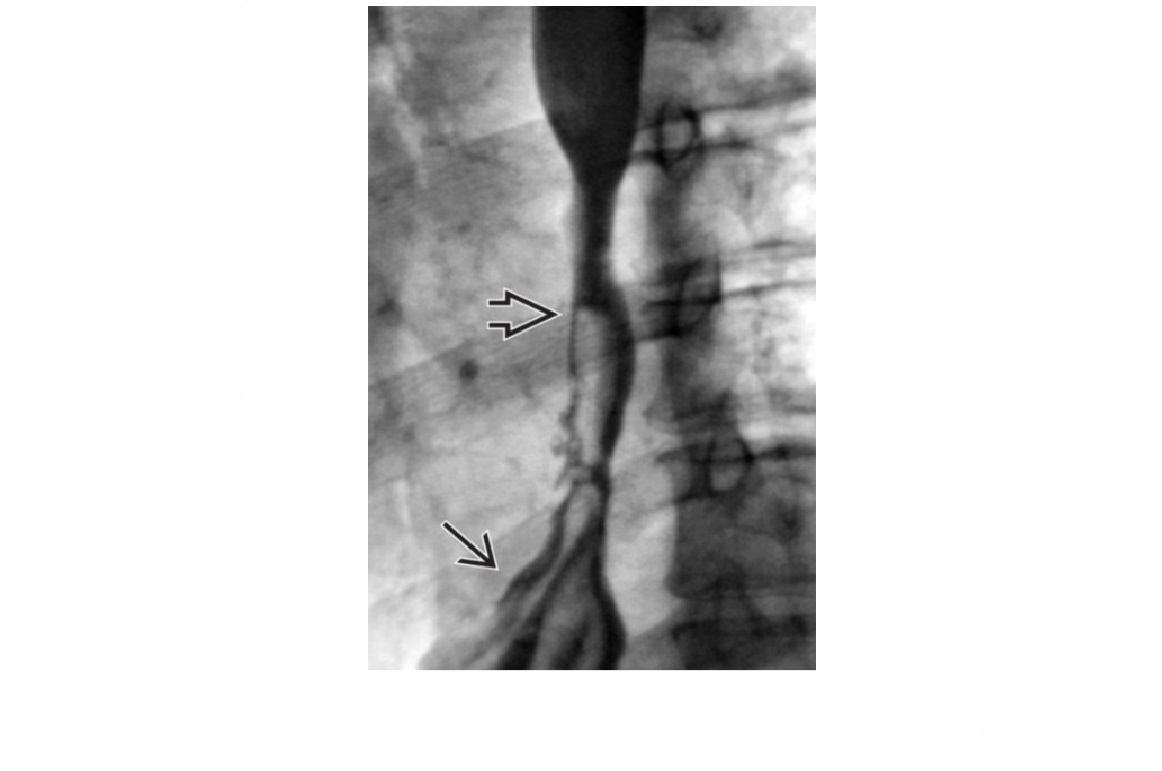

oesophageal scleroderma

-affects the Lower 2/3 (smooth muscle) with atony and peristalsis that begin caudally and moves cranially.

-Moderate dilatation of esophagus with fusiform stricture at lower end

Nb upper 1/3 to above aortic arch is normal (striated muscle)

DDx

Achalsia

- Grossly dilated whole oesophagus with smooth, beak-like tapering at lower end

Reflux Esophagitis (With Stricture)

-Longer tapered distal stricture

-Less luminal dilation

-Distinguished from scleroderma by normal peristalsis

Esophageal Carcinoma

-Abrupt proximal borders of strictured segment (rat tail appearance)

-Mucosal irregularity, shouldering, mass effect